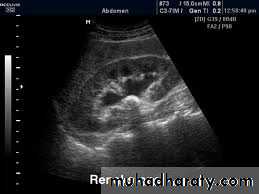

Ultrasound findings

1-Dilatation of the P.C.S. appears as multilocular fluid collection within central echo complex.

-With more severe distention, dilated calyces appear as

Multiple cysts but communicating with each other unlike true cysts.

2-Stones larger than 5mm are easily seen on US but smaller ones may be missed.

-They produce intense echoes (hyperechoic) and cast acoustic shadows.

-Proximal and distal ureteric dilatation can be easily identified unlike mid-ureteric dilatation, and stones located in the middle third of the ureter are hard to be demonstrated unlike upper and lower ureteric stones (especially those lodged in the vesico-ureteric junction or pelvi -ureteric junction) which are easily identified by ultrasound.